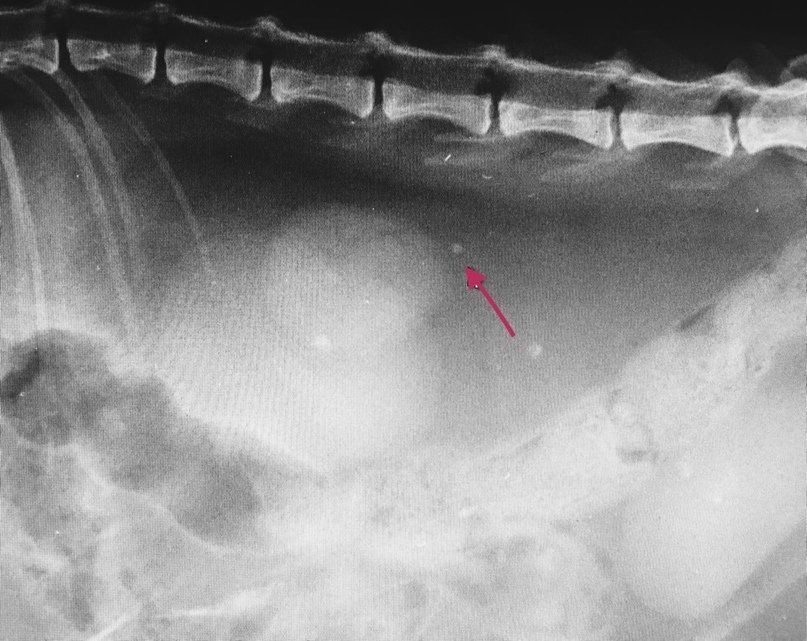

• Рентген диагностика для оценки наличия уролитов (камней) в мочеточниках и почках

Уролиты на рентгене